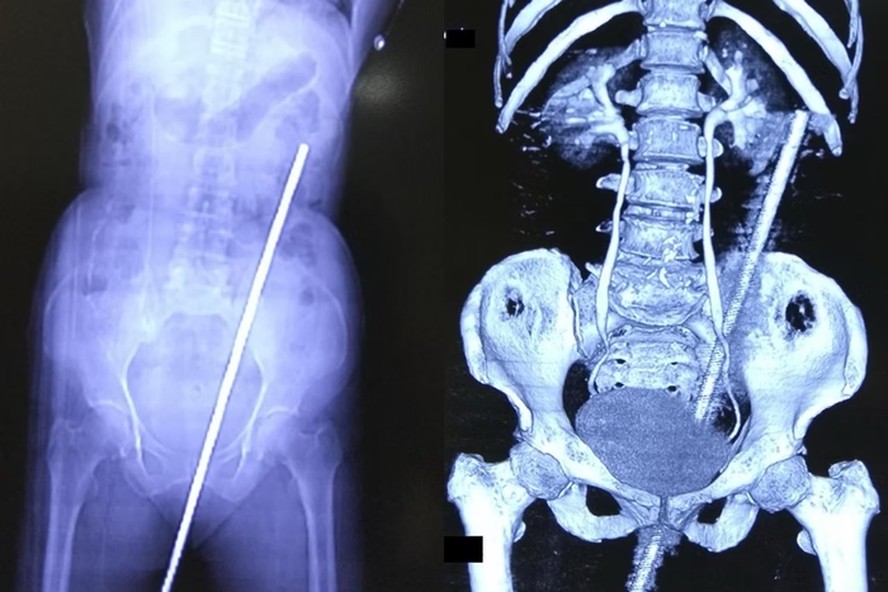

| O objeto entrou pelo reto da mulher, causando uma perfuração que se estendeu até as costas — Foto: Reprodução/ International Journal of Surgery Case Reports |

Uma senhora indiana de 65 anos deu entrada no hospital empalada com uma barra de metal enferrujada de quase 60 centímetros. O acidente aconteceu quando ela escorregou no campo e caiu em cima do artefato, que estava parcialmente enterrado no solo.

O caso foi publicado no International Journal of Surgery Case Reports. A idosa foi encontrada gritando de dor e sem conseguir se locomover. O objeto entrou pelo reto da mulher, causando uma perfuração que se estendeu até as costas.

Segundo os médicos, não houve danos a órgãos internos e nem mesmo aos vasos sanguíneos. A mulher recebeu antibióticos e uma vacina contra tétano para prevenir infecções, visto que o metal estava enferrujado, coberto de lama e com esterco de vaca.

Ela precisou ainda passar por uma cirurgia de duas horas para remover a barra. O caso, segundo a equipe médica, é extremamente raro, ainda mais por não ter causado danos graves ou permanentes. A mulher recuperou a mobilidade e a dor desapareceu após alguns dias. Recebendo alta do hospital.